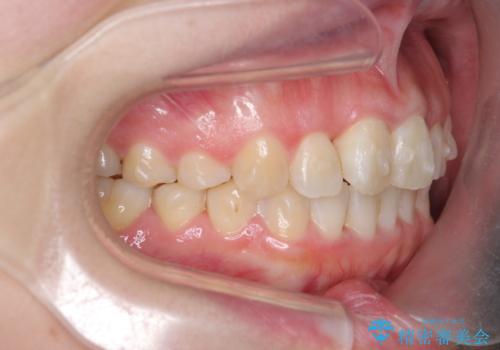

- 前歯のねじれを改善したい、と矯正治療を希望され来院されました。

上下の歯のがたつきを改善するマウスピース矯正治療と、下顎に見られる大きな骨隆起を外科的に除去する治療計画を進めていきます。